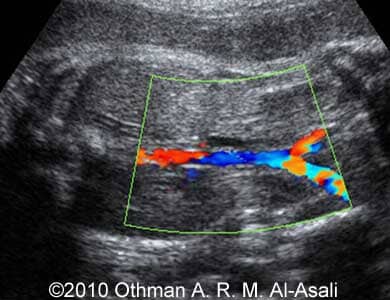

Images 3,4: Doppler imaging of the umbilical cord, note the absence of the amniotic fluid pocket.